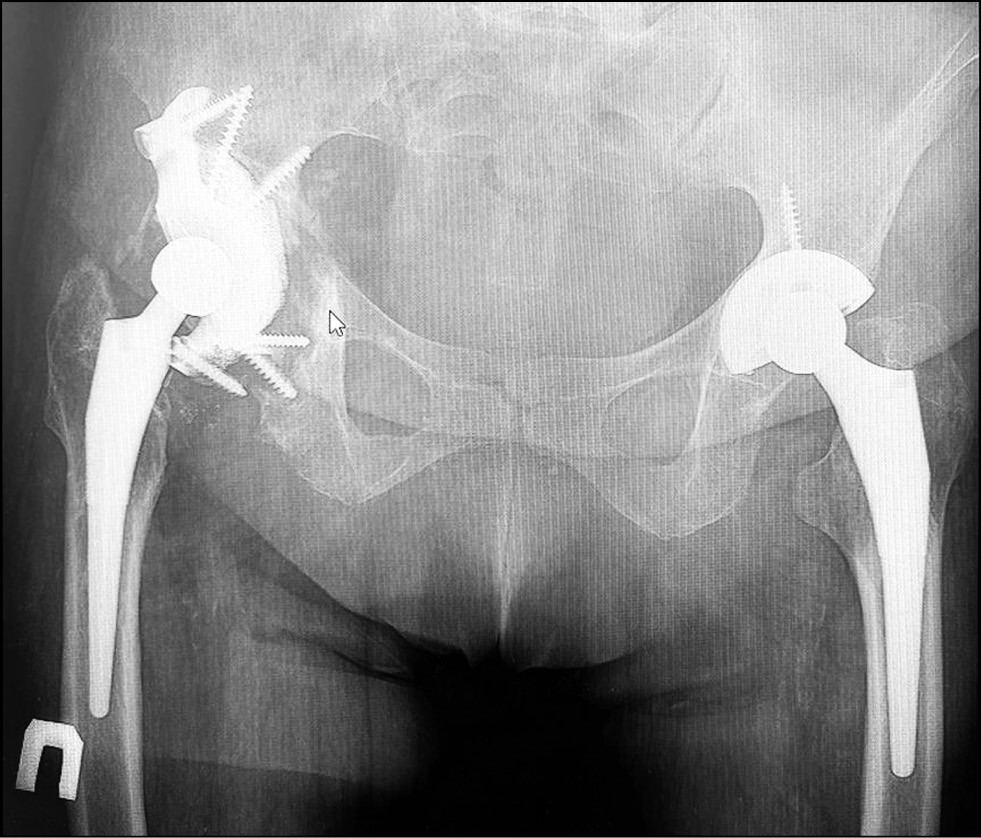

The final digital model of the implant was printed on a 3D printer (Fig. 4), sterilized by autoclaving, and inserted (Fig. 5). The implant position was assessed on postoperative radiographs (Fig. 6). Postoperatively, the patient received symptomatic, anticoagulant, antibacterial, and rehabilitation therapy, and the wound healed with primary tension. The patient was discharged on day 7 after surgery.

Fig. 6. Postoperative control X-ray.

Three months after surgery, the patient came for a follow-up examination. Radiographs showed migration of the sciatic and brow bones from the flanges of the construct (Fig. 7). The patient still had pain syndrome in the operated joint area, which was 28 (mm) points on the VAS scale. On the HHS scale, the hip joint function was assessed at 75 points. The social adaptation score on the WOMAC scale was 38 points. Considering the clinical and radiological picture, the patient was offered surgery for screw removal from the lower flanges and correction of the sciatic flange of individual design with a high-speed bur. The patient refused the proposed surgery.

Fig. 7. Postoperative control X-ray after 3 months.

Six months after surgery, no negative dynamics on control radiographs were observed. The HHS, WOMAC, and VAS scores were 82, 15, and 30 (mm) points, respectively. Despite a slight increase in the severity of pain syndrome according to the VAS score, the patient noted improvement in the bearing capacity and functional results of the operated limb. No significant changes in the evaluation scales were noted at the subsequent follow-up examinations (1 year after surgery and once a year thereafter). At the time of writing, >4 years have elapsed since the operation. Data obtained four years after surgery did not show negative dynamics on control radiographs (Fig. 8). The pain syndrome slightly increased and corresponds to 32 (mm) points on the VAS scale. On the HHS scale, the hip joint function corresponded to 74 points, and social adaptation according to the WOMAC scale corresponded to 35 points. The patient is under dynamic observation.